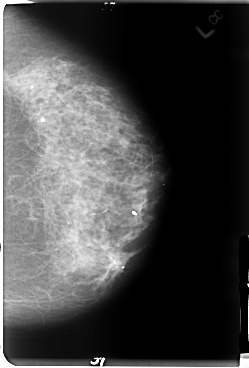

B_3054_1.LEFT_CC

LEFT_CC LINES 4776 PIXELS_PER_LINE 3232 BITS_PER_PIXEL 12 RESOLUTION 50 NON_OVERLAY